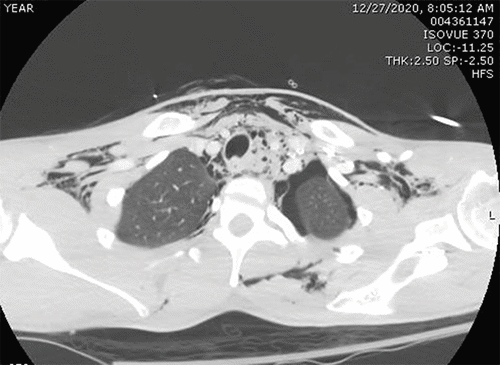

Repeat chest CTA revealed a localized air-fluid collection in the left hemithorax, concerning for empyema. However, imaging review suggested an anatomic variant: a posteromedially positioned thoracic duct coursing along the left aorta, lateral to the vertebral column. Given this anomaly, a second IR embolization attempt was undertaken. Accessing the thoracic duct via the left neck proved challenging due to its proximity to the subclavian junction. Therefore, we opted for a re-approach of the previously embolized cisterna chyli through the epigastrium, followed by successful repeat embolization with glue (Figures 7-10).

Figure 9. Repeat Access to Thoracic Duct. Published with Permission

The arrow indicates the placement of the catheter within the thoracic duct. Extravasation of contrast is noted at the puncture site in the cisterna chyli